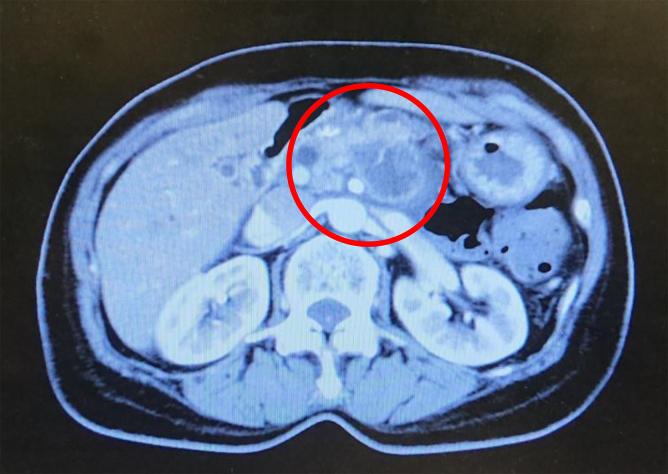

Splanchnic nerve block is considered to be effective for abdominal visceral pain, and is performed for the purpose of controlling abdominal pain and back pain caused by upper abdominal cancer. The patients in this case report were candidates for splanchnic nerve block owing to cancer-associated pain. However, because they could not assume the prone position that is required for the block owing to their pain, combined epidural anesthesia was used, resulting in successful implementation of the splanchnic nerve block. Patients who are candidates for splanchnic nerve block often have advanced cancer, and it is hence often difficult to secure and maintain the position required for the procedure owing to their severe pain. The two patients presented here suggest the possibility that epidural anesthesia might be useful as an adjunct in such cases.

内脏神经阻滞被认为对腹部内脏疼痛有效,其实施目的是控制上腹部癌症引起的腹痛和背痛。本病例报告中的患者因癌症相关疼痛而成为内脏神经阻滞的候选对象。然而,由于疼痛,他们无法采取阻滞所需的俯卧位,因此采用了联合硬膜外麻醉,从而成功实施了内脏神经阻滞。内脏神经阻滞的候选患者通常患有晚期癌症,因此由于疼痛严重,往往难以确保并维持该操作所需的体位。此处介绍的两名患者表明,在这种情况下硬膜外麻醉作为辅助手段可能有用。